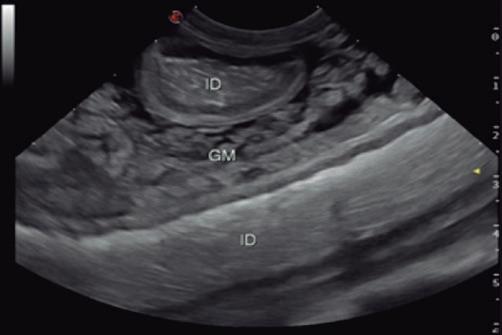

La radiología intervencionista, también conocida como radiología vascular e intervencionista, es una especialidad que se encarga del diagnóstico y tratamiento de una gran cantidad de enfermedades de una manera mínimamente invasiva. Se realiza mediante un abordaje guiado por distintas técnicas de imagen como, por ejemplo, la ecografía, la fluoroscopia o la tomografía computarizada, para alcanzar la zona a diagnosticar o tratar.

imágenes basadas en rayos X y posteriormente las convierte en una señal de vídeo en tiempo real. Estas imágenes pueden manipularse ofreciendo funciones como la angiografía de sustracción digital, mapeo vascular y ampliación. Respecto a una radiografía, la exposición de rayos X necesaria para realizar una fluoroscopia es baja, pero debido a la duración de las series de imágenes que habitualmente se toman, el nivel de exposición en los pacientes suele ser elevado. Por lo tanto, es importante controlar el tiempo de exposición y llevar un registro de este. El fluoroscopio debe estar situado en una sala adecuada para su uso seguro, y todo el personal que entre en la sala de fluoroscopia debe protegerse de la radiación utilizando un delantal plomado, protectores de tiroides y gafas plomadas.